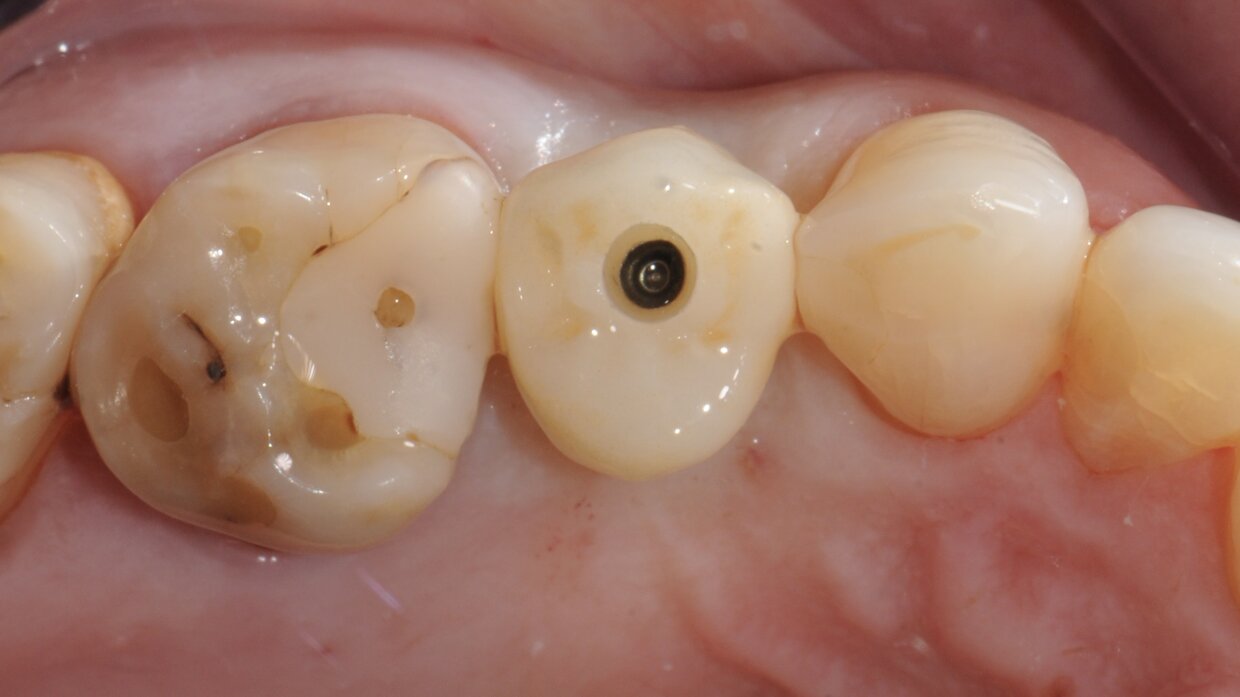

Impianto con tecnica Flapless

Minimamente invasivo, senza lembo chirurgico nè punti di sutura

Il posizionamento degli impianti è stato pianificato prima dell'intervento su un software dedicato. In un'unica seduta, dopo l'estrazione degli elementi dentari compromessi, sono stati immediatamente inseriti gli impianti nella posizione pianificata, grazie alla realizzazione della dima chirurgica. Per ridurre il riassorbimento osseo a lungo termine e garantire quindi una maggiore resa estetica (vista la zona d'intervento), la chirurgia è stata eseguita con una particolare tecnica denominata: Socket Shield Technique.